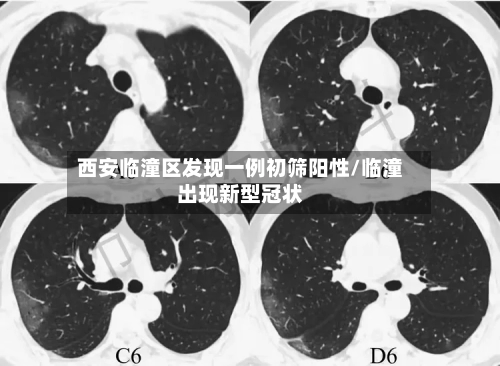

西安临潼区发现一例初筛阳性/临潼出现新型冠状